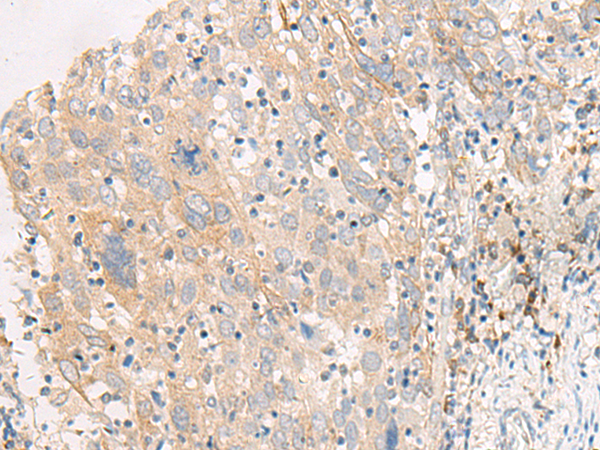

IHC positive control: |

Human cervical cancer |